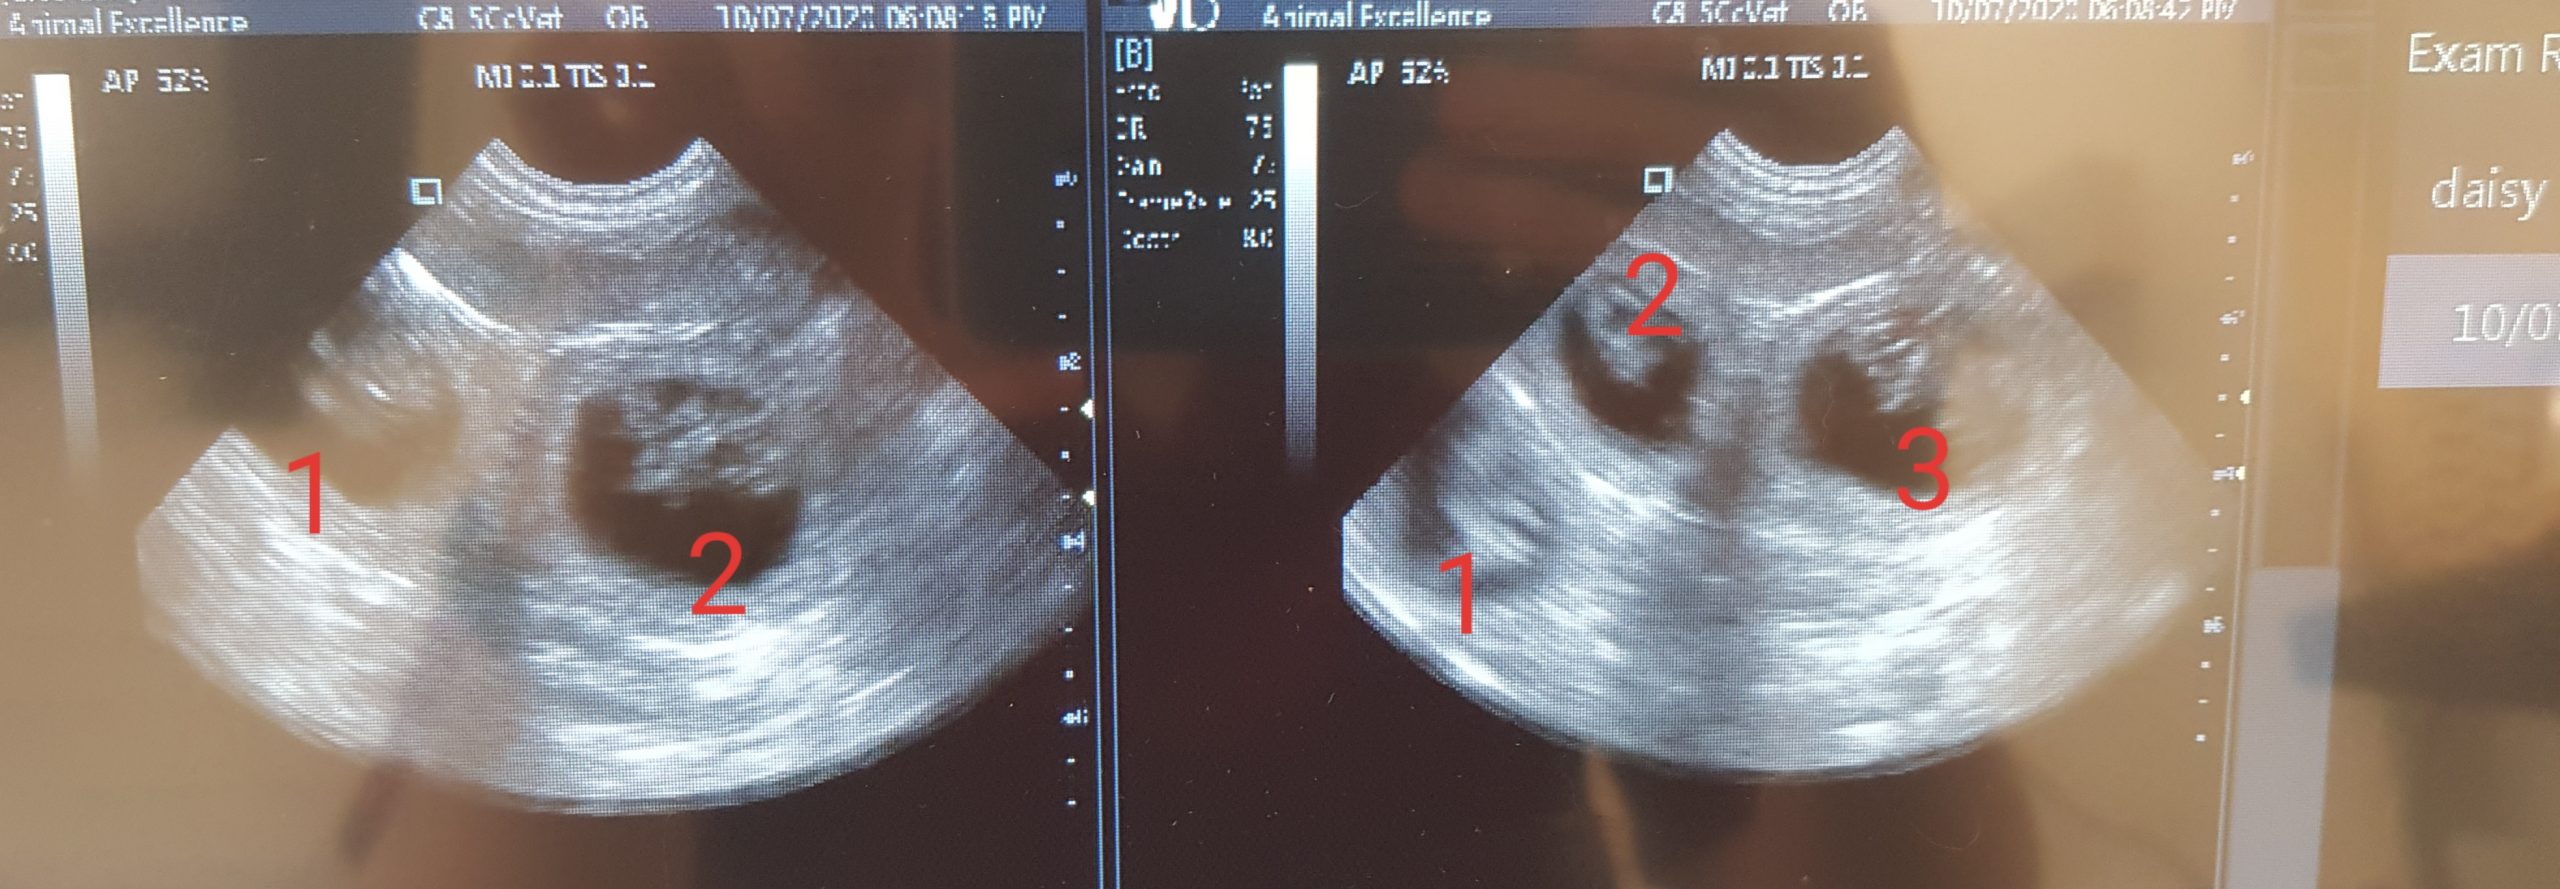

Pyometra- Accidental finding on ultrasound six weeks from mating

Here you see a scan image of Pyometra, it was an Accidental finding on ultrasound 6 weeks from mating, The scan was preformed to check for pregnancy but in this